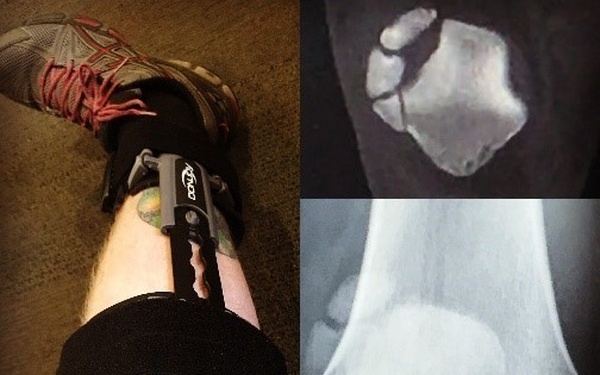

Soldier says you’re not less of a person for landing in a WTU